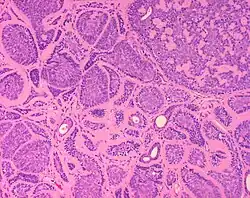

Dermal cylindromas are:

- Dermal lesions consisting of nests of cells that are surrounded by hyaline (i.e., glassy, eosinophilic, acellular) material and have:

- Hyperchromatic nuclei that may palisade (columnar nuclei arranged around the periphery of the cell nests with their short axis tangential to the nest periphery), and

- Cells with lighter staining ovoid nuclei at their centre.

They lack of a significant number of lymphocytes; this differentiates them from spiradenomas.

Micrograph of a dermal cylindroma in H&E stain. -

Micrograph of dermal cylindroma in H&E stain. -